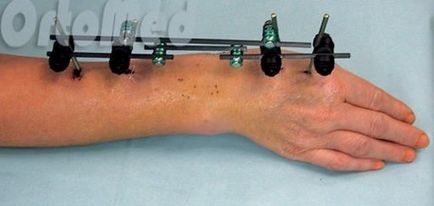

Премахване spitsesterzhnevogo апарат appatata Ilizarov хирургия

Отстраняването на устройството Ilizarov не е трудно, защото спиците и пръти, разположени над кожата. След извършване на обща или местна анестезия, се извършва "skusyvanie" спици и да ги извадите от костите. В присъствието на барове, те могат да се оказа. Рани, лекувани с антисептични разтвори, налагат асептична превръзка.